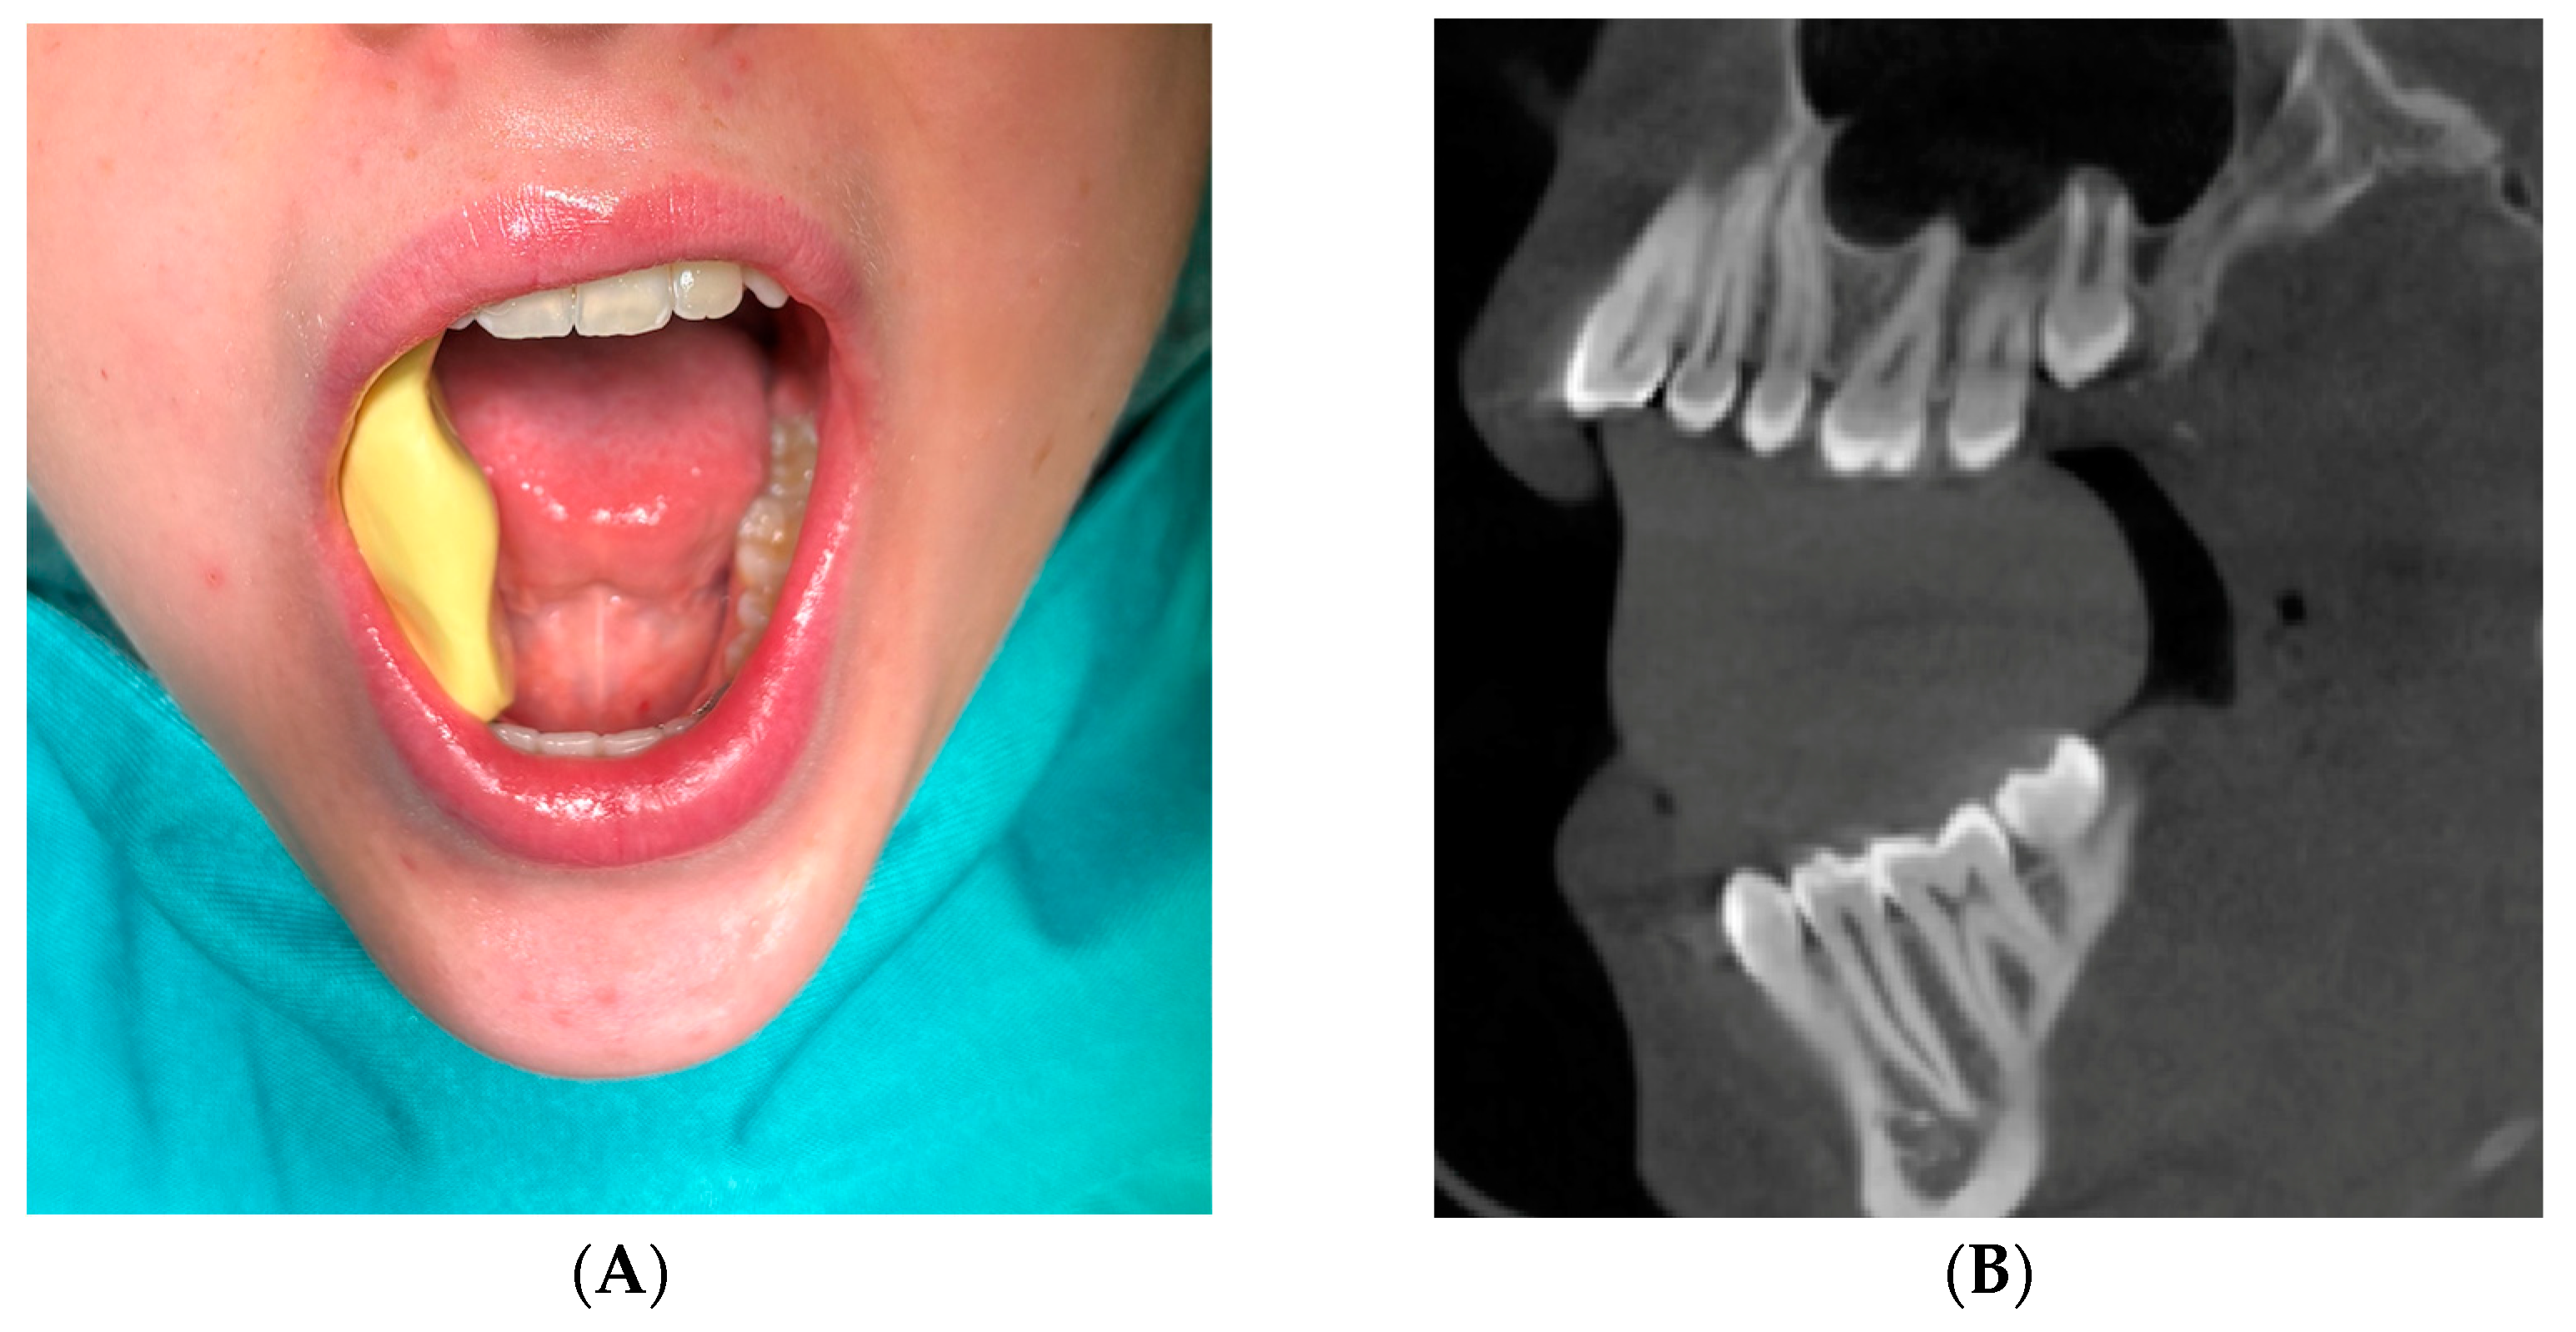

1. Introduction

2.3. Clinical Patients

2.7. Surgery